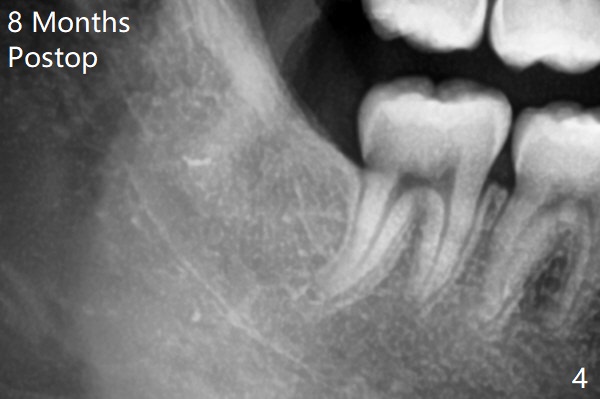

1.5年智齿牙根长长(图二)。1.5月后下颌智齿拔除放置Osteogen Plug(图三)。八个月后牙槽窝愈合(图四)